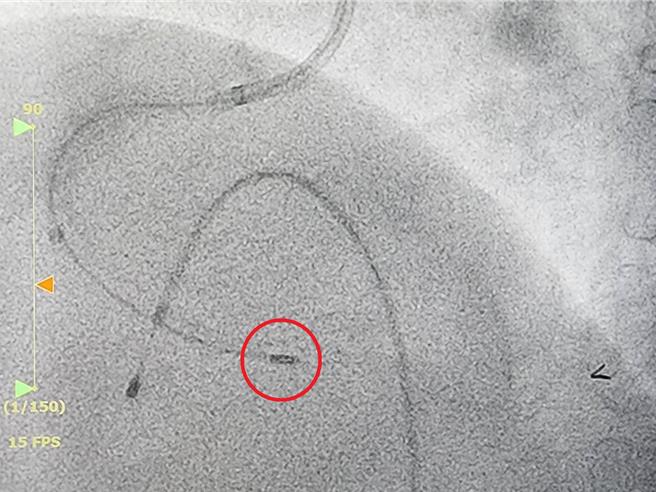

冠状动脉旋磨术使用高速旋转的金刚石包覆钻头(红圈处),磨除血管内的钙化斑块。(大千医院提供/吕丽甄苗栗传真)

根据大千综合医院心臟内科医师罗健贤的说法,冠状动脉旋磨术是一种专门处理高度钙化或导管器材无法通过病灶的复杂技术。该技术使用高速旋转的金刚石包覆钻头,以每分钟15-22万转的速度磨除血管内的钙化斑块,将其转化为极微小的颗粒,并被人体自然吸收。